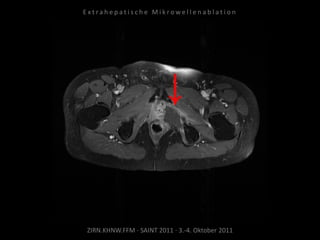

Ablation am 25.03.2010:

1 Nadelposition, 45 W, 7 Min.

Während der Ablation werden

Harnleiter, Harnblase und Rektum

zwecks Hitzeableitung gespült zur

Vermeidung thermischer Schäden.

Kontrolle:

MRT 06.04.2010